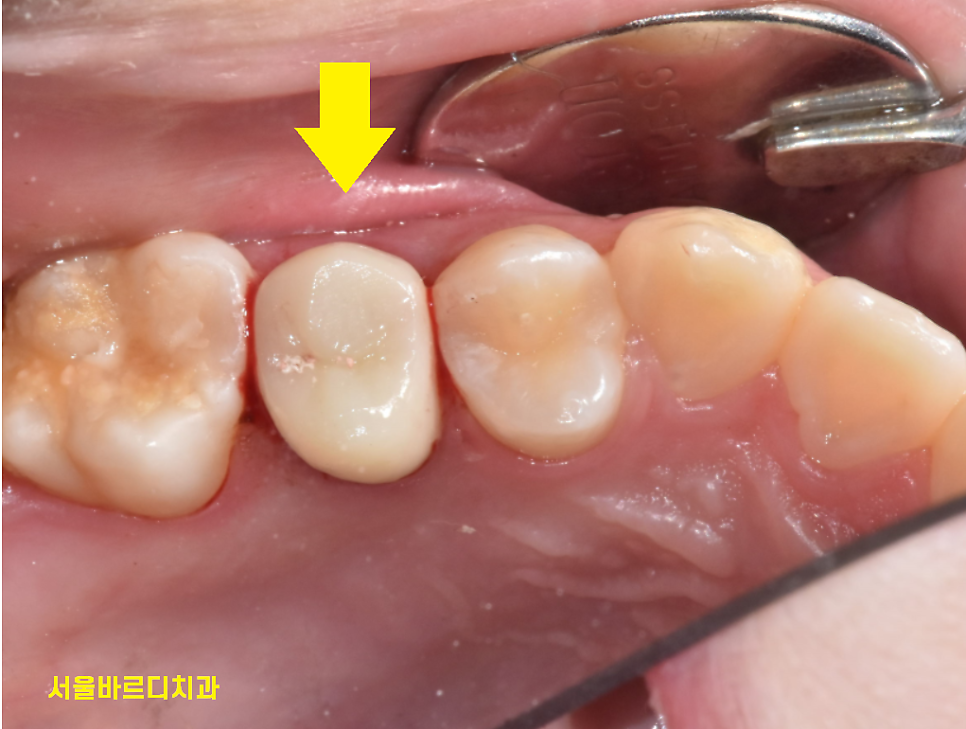

한쪽 부분이 잇몸에 박힐 정도로

많이 부러져서

잇몸도 절제하고

보철물 제작을 시행하였는데요.

231215

작은 어금니라 힘을 많이 받지 않는 부위라

살려 볼 수 있었습니다.